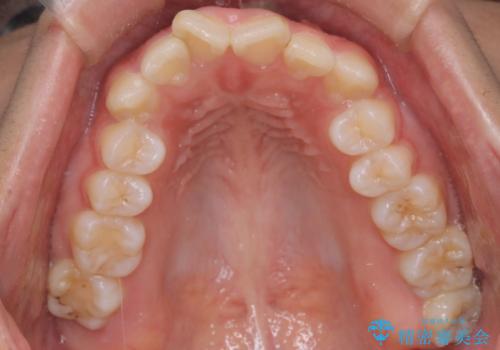

- 歯のデコボコ(叢生)を気にされて来院されました。精密な検査の結果、中等度の叢生と診断。患者様のご希望に合わせ、透明で目立ちにくい**インビザライン(マウスピース矯正)**による治療計画を立案しました。歯を抜かずに、歯列弓(歯が並ぶアーチ)を少しずつ拡大することで、歯が並ぶスペースを確保し、叢生を改善することを目指します。

今回の矯正治療では、透明なマウスピース型の装置インビザラインを使用しました。この装置は目立ちにくく、取り外しが可能なため、食事や歯磨きも普段通りに行えます。治療は、緻密に計算された治療計画に基づき、段階的に作製されたマウスピースを交換していくことで、歯列弓全体を徐々に広げていきました。この歯列弓の拡大により、不足していたスペースを確保し、歯のデコボコを効果的に解消。抜歯することなく、整った美しい歯並びと良好な咬み合わせを獲得していただけました。